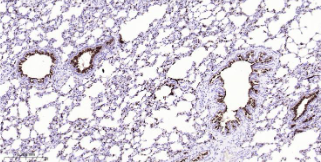

Immunohistochemical analysis of paraffin embedded Rat lung tissue slide using IHC0549R (Rat MUC1 Kit).